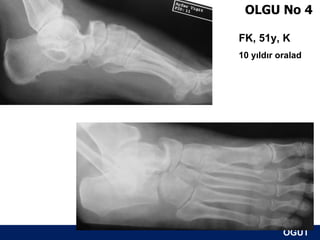

OLGU No 4

FK, 51y, K

10 yıldır oralad